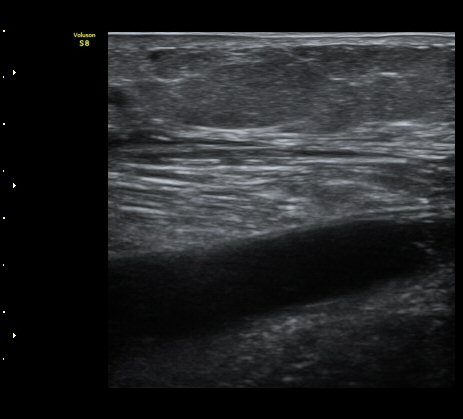

³»Ãøºñº¹±Ù°ú °¡Àڹ̱٠»çÀ̰¡ ¹ú¾îÁö°í ¼ö¾×ÀÌ Àú·ùµÊ.

ÃÊÀ½ÆÄ À¯µµÇÏ ¼ö¾× ÈíÀÎ(÷ºÎ µ¿¿µ»ó) ÈÄ ¾Ð¹ÚºØ´ë °íÁ¤.

³»Ãø ºñº¹±Ù ÆÄ¿Àº ´ë°³ ±Þ¼ºÀ¸·Î ¹ß»ýÇÏ¿© °æÇèÀÌ ÀÖ´Â ÀÇ»ç´Â ºñº¹±ÙÆÄ¿À» ÃßÁ¤ÇÒ ¼ö ÀÖ´Ù.

±×·¯³ª °æ¹ÌÇÑ ÆÄ¿ ÈÄ ¹«¸®ÇÑ ¿îµ¿À¸·Î ÆÄ¿ÀÌ ÁøÇàµÇ´Â °æ¿ì ÅëÁõÀÌ Å©Áö ¾Ê°í º´·Âµµ ¶Ñ·ÈÇÏÁö ¾Ê¾Æ

ºñº¹±Ù ÆÄ¿À» ÃßÁ¤ÇϱⰡ ½±Áö ¾Ê´Ù. ÀÌ·± °æ¿ì¿¡´Â È®Áø¿¡ ÃÊÀ½ÆÄ°Ë»ç°¡ ÇʼöÀûÀÌ´Ù.